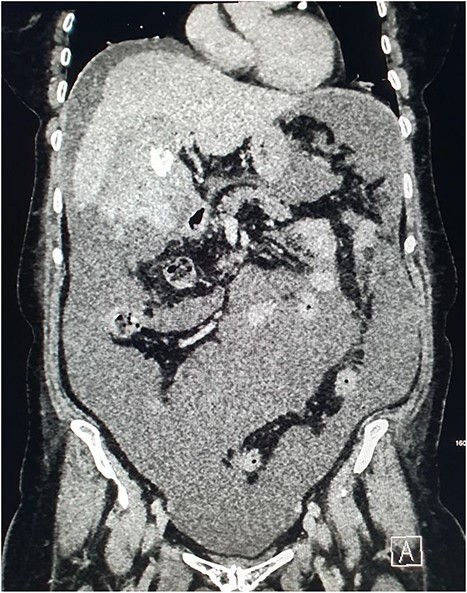

Magnetic resonance imaging (MRI) of the liver and magnetic resonance cholangiopancreatography (MRCP) were performed in the following days, which demonstrated a frank rupture of the gallbladder and a patent biliary tree (Fig. 3). After a few more days, the patient became peritonitic and a further CT was performed. This demonstrated a moderate volume of peritoneal free fluid and haematoma in the gallbladder fossa (Fig. 4). Ultrasound-guided drainage of peritoneal fluid was performed producing bilious fluid. ERCP was performed, which demonstrated ongoing leak from the gallbladder fossa (Fig. 5) and allowed placement of a covered biliary stent to divert flow away from the cystic duct.

CT demonstrating large volume of bilious peritoneal fluid with haematoma and calculus in the gallbladder fossa.

CT of the abdomen was performed the following week due to pyrexia and ongoing pain. This demonstrated abscess formation at the site of haematoma in the gallbladder fossa (Fig. 6). A locking pigtail drain was placed in the gallbladder fossa collection under ultrasound guidance. Slow drainage of bloodstained bilious fluid from the right upper quadrant with resolution was demonstrated on CT the following month (Fig. 7). The patient was discharged with gallbladder (GB) fossa drain and biliary stent in situ to await elective cholecystectomy.